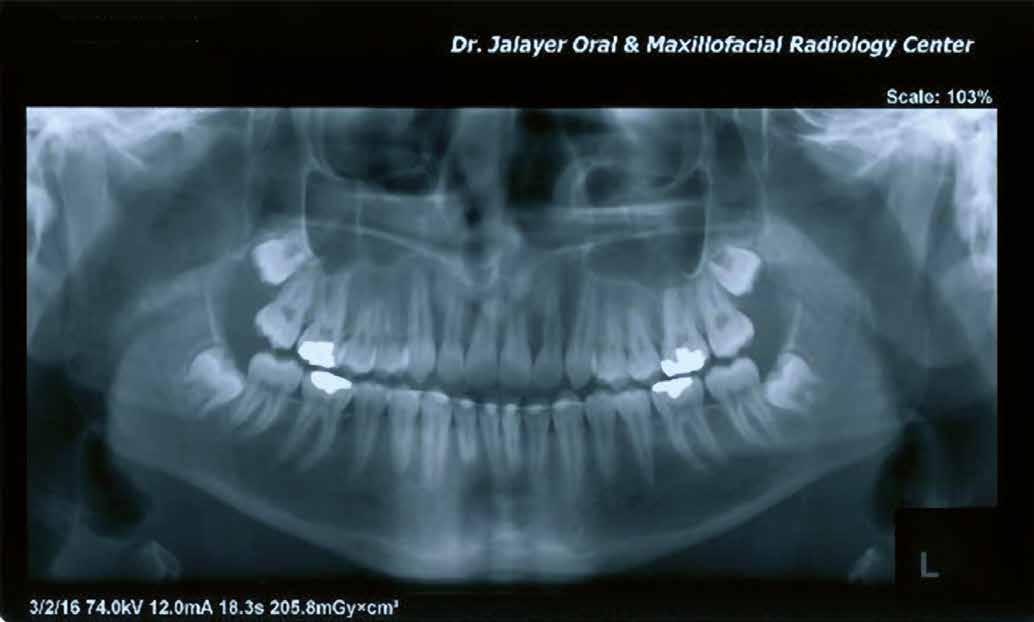

A 10 éves férfi páciens a felső frontfogai késői/nem megvalósuló előtörése miatt kereste fel a rendelőnket. A klinikai és a radiológiai vizsgálat során a jobb felső nagymetszőfog impakcióját észleltük (1. ábra). A fog horizontális tengelyállással és dilacerált gyökérrel rendelkezett. A felső dentális középvonal a fogak vándorlása miatt jelentős mértékben elcsúszott. A bal felső kismetszőfog is rendkívül kedvezőtlen pozícióba került.

Dr. Kazem Dalaie, dr. Samin Ghaffari, dr. Mazir Mir (Irán, Németország) 1. a ábra: Az intraorális felvételen jól látható a jobb felső nagymetszőfog lehetséges impakciójára utaló foghiány.

1. b ábra: A panoráma röntgenfelvételen megfigyelhető a teljes impakcióban lévő jobb felső nagymetszőfog. 1. c ábra: A CBCT felvétel is igazolja a jobb felső nagymetszőfog impakcióját.